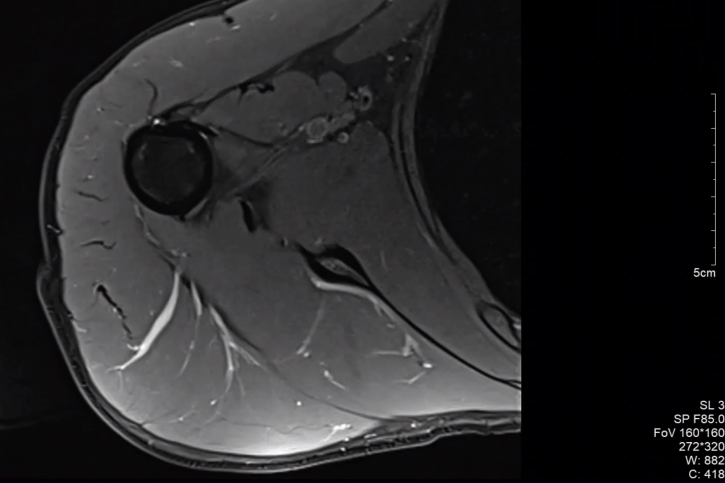

Staw ramienny to struktura, która charakteryzuje się bardzo dużą mobilnością, jedną z największych ze wszystkich stawów. Duża ruchomość jest wynikiem odpowiednio dobranych powierzchni stawowych (rozległa powierzchnia stawowa na głowie kości ramienna oraz płytka powierzchnia stawowa łopatki), a także luźnego aparatu torebkowo-więzadłowego. Tak duża ruchomość w stawie daje ogromne możliwości funkcjonalne dla kończyny górnej, ale odbywa się niejako kosztem stabilności stawu, co sprawia że jest on podatny na urazy i przeciążenia.